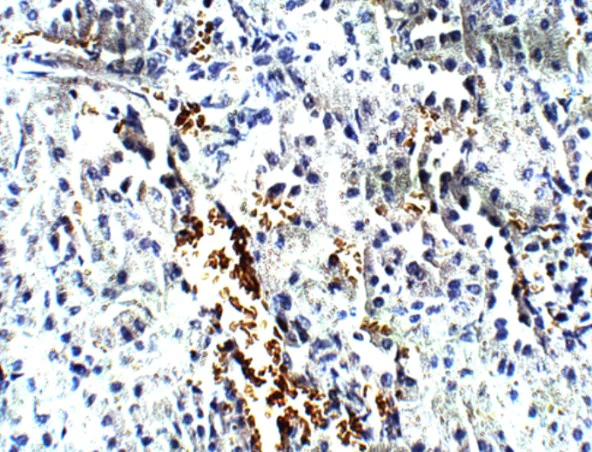

Immunohistochemistry (Formalin/PFA-fixed paraffin-embedded sections) - Anti-FOXP3 antibody (AB75763)

Immunohistochemistry (Formalin/PFA-fixed paraffin-embedded sections) of Mouse kidney tissue staining FOXP3 using ab75763 at 1/100. DAB staining (brown) Hematoxylin QS counterstain (blue).